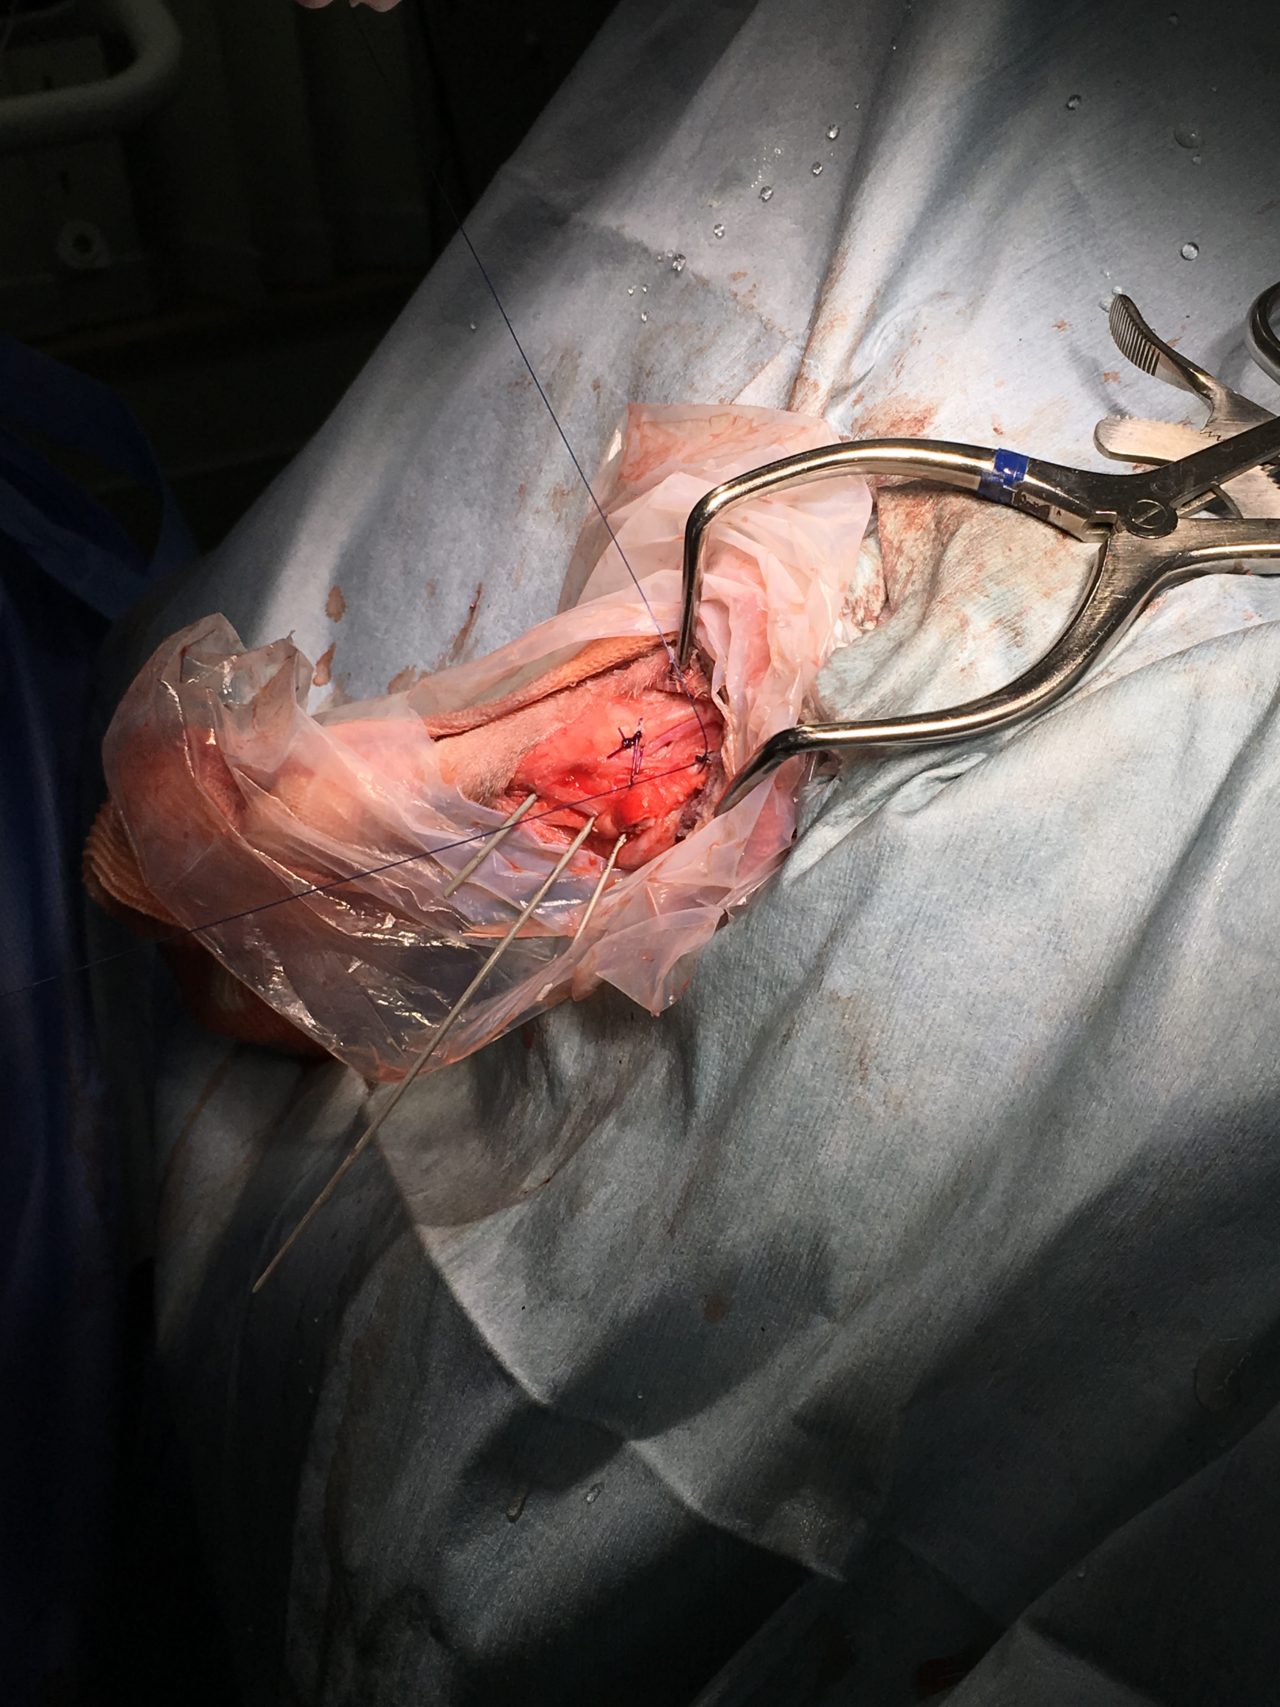

アキレス腱断裂 主治医よりアキレス腱断裂した患者さんが脚を着けなくなったので、なんとかして欲しいと連絡がありました。経関節ピンによる一時的な足根関節の仮固定とアキレス腱の縫合術により対応しました。しばらくは安静が必要です。 症例カテゴリー 放射線治療整形外科軟部組織外科脳神経外科内科腫瘍外科救急・集中治療リハビリテーション科腫瘍内科内視鏡科脳神経科呼吸器外科中医・漢方猫の腎移植循環器科